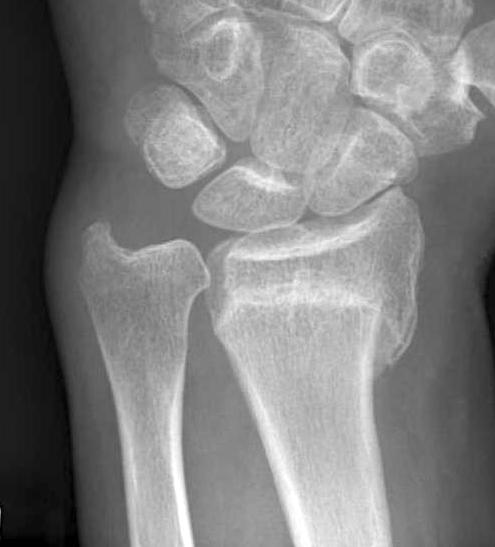

Xray

Bilateral xrays

PA film in neutral

- wrist neutral

- elbow & shoulder at 90°

Malunion

| Radial shortening | Radial inclination | Positive ulna variance |

| Dorsal tilt > 15 degrees | Volar tilt > 10 degrees | Articular step > 3 mm |